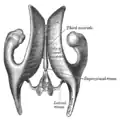

Обзорное изображение боковых желудочков, сверху

Обзорное изображение боковых желудочков, сверху Центральная часть, передние и задние рога боковых желудочков, сверху

Центральная часть, передние и задние рога боковых желудочков, сверху Корональный срез через задние рога боковых желудочков

Корональный срез через задние рога боковых желудочков Корональный срез через передние рога боковых желудочков